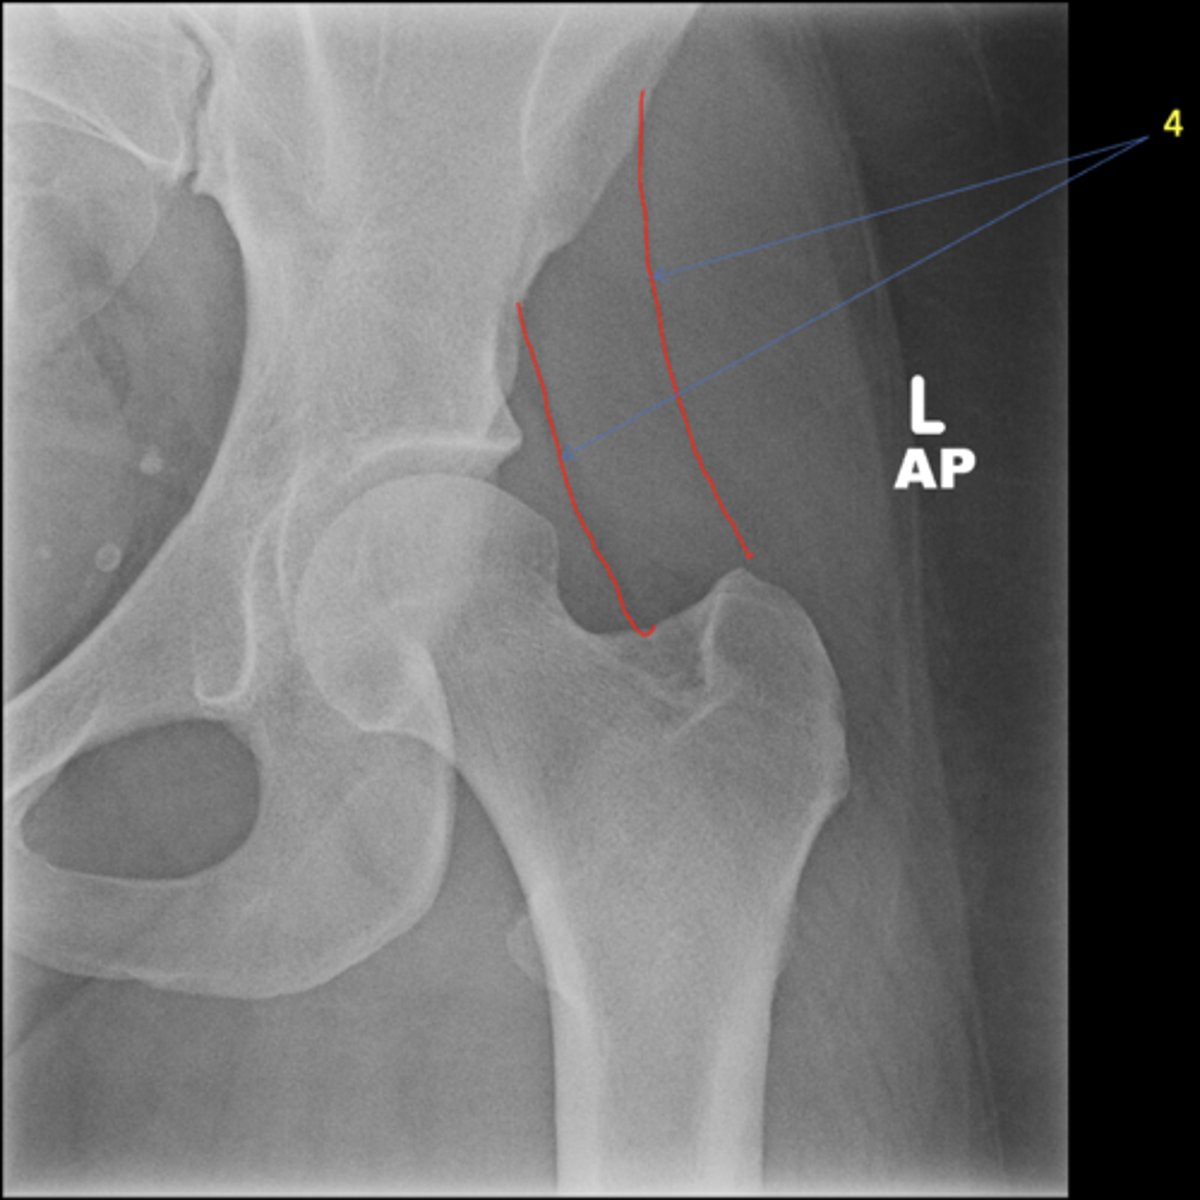

New cards

Left AP hip

View?

<p>View?</p>

29

Phleboliths

ID 1

<p>ID 1</p>

30

Obturator foramen

ID 2

<p>ID 2</p>

31

Kohler's teardrop

ID 3

<p>ID 3</p>

32

Gluteus medius

ID 4

<p>ID 4</p>